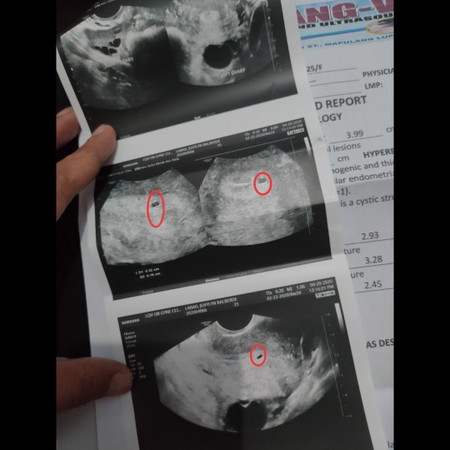

hello po.. sino same case ko dito na ganito result ng transv. may nakkita sa loob ng ovary ko pero gumagalaw sya ndi. pa masabe kung bata o bukol kc ndi pa sya makita.. nakkita lang gumagalaw sya sa loob ng ovary ko.. pls comment po sa same case ko dito salamat po

pakita mo nlng po ung report ng trans v mo sis.. bka po you mean sa loob ng uterus hindi sa ovary?